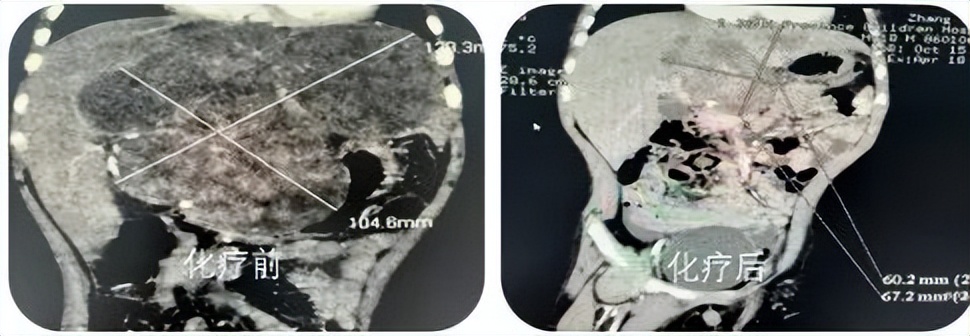

- 新辅助化疗: 与成人肝癌相比, 90%肝母细胞瘤对化疗敏感 ,通常经过1-2疗程化疗,肿瘤可缩小一倍以上,甲胎蛋白呈数倍下降,经过4个疗程化疗后肿瘤坏死缩小明显,再进行手术,切除组织减少,肿瘤活性明显减低,术后肿瘤复发、肝功能损伤等并发症明显减少,再加上术后规范化疗,预后较好。